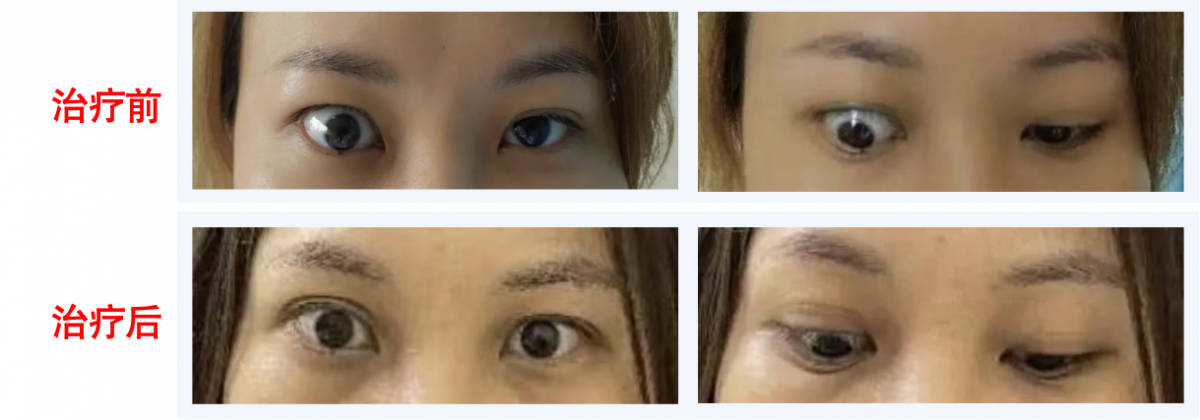

★甲状腺眼病MDT诊疗

甲状腺眼病又称Graves眼病,其典型表现为眼睑挛缩、眼球突出、畏光流泪、眼球疼痛、复视、视力下降等,影响外观,甚至危及视力,严重影响患者生活质量。

亚专科联合相关学科成立了甲状腺眼病(眼科、耳鼻喉科、甲乳外科、核医学科、超声科、放疗科、放射科等)MDT团队,以患者为中心,内分泌科医师主导,MDT团队全程协作,为疑难复杂甲状腺眼病患者制定精准治疗方案,获得广大患者好评。